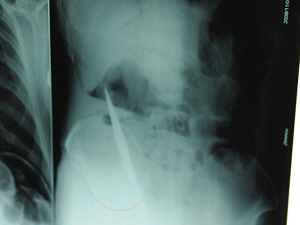

X光片上,尖刀清晰可見。

從男子體內(nèi)取出的尖刀足足有19厘米長。

6日上午,記者在徐州礦務(wù)集團(tuán)總醫(yī)院重癥監(jiān)護(hù)室見到了這名男子,目前他雖然已經(jīng)恢復(fù)了意識(shí),但還不能開口說話,需要呼吸機(jī)輔助呼吸。據(jù)醫(yī)生介紹,4日中午12時(shí)左右,這名男子因服毒輕生被緊急送到醫(yī)院進(jìn)行搶救,之前,這名男子已經(jīng)在當(dāng)?shù)剜l(xiāng)鎮(zhèn)醫(yī)院進(jìn)行了近20小時(shí)的治療,但效果不佳!安∪吮晦D(zhuǎn)院到礦總院時(shí)已神志不清,血壓極低,處于休克狀態(tài)。”救護(hù)人員給男子洗胃、初步處理以后,發(fā)現(xiàn)男子呼吸急促,于是趕緊給他拍片檢查。結(jié)果讓所有的醫(yī)生大吃一驚,竟有一把尖狀異物橫在該男子腹腔內(nèi)!當(dāng)天下午5時(shí)30分,輕生男子被推上了手術(shù)臺(tái)。經(jīng)過40多分鐘的手術(shù),該男子腹腔被打開,手術(shù)醫(yī)生發(fā)現(xiàn),男子體內(nèi)的金屬狀異物竟然是一把長19厘米的尖刀!